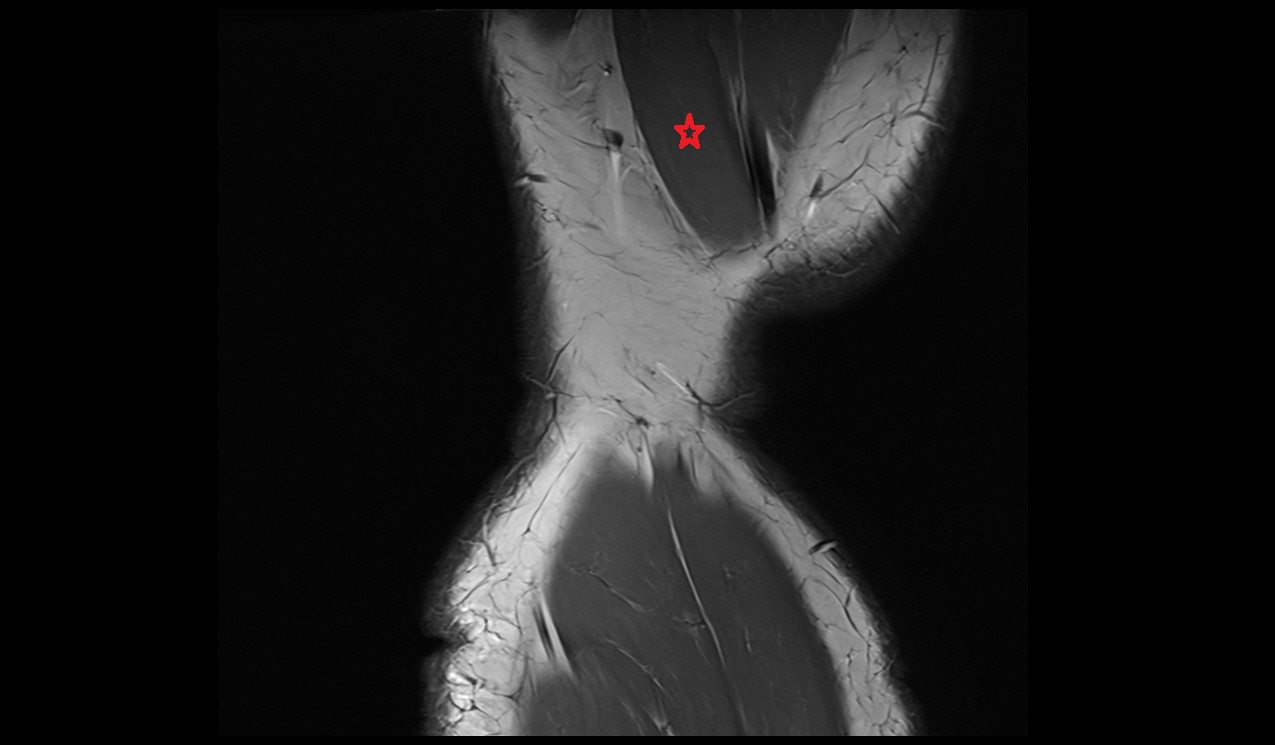

- Achilles tendon

- Plantaris tendon

- Abductor hallucis tendon

- Tibialis posterior tendon

- Tibialis posterior muscle

- Flexor digitorum longus muscle

- Flexor hallucis longus muscle